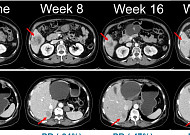

- 코오롱생명과학, 항암 유전자치료제 ‘KLS3021’ 피부암 연구 국제 학술지 게재

- 코오롱생명과학은 항암 유전자치료제 후보물질 KLS-3021의 피부 편평세포암(cSCC) 전임상 연구 결과가 세포·유전자치료 분야 국제학술지인 ‘Molecular Therapy Oncology’에 최종 게재됐다고 27일 밝혔다. KLS-3021은 암세포 선택성을 높인 재조합 백시니아 바이러스에 치료 유전자(PH-20, IL-12, sPD1-Fc)를 탑재